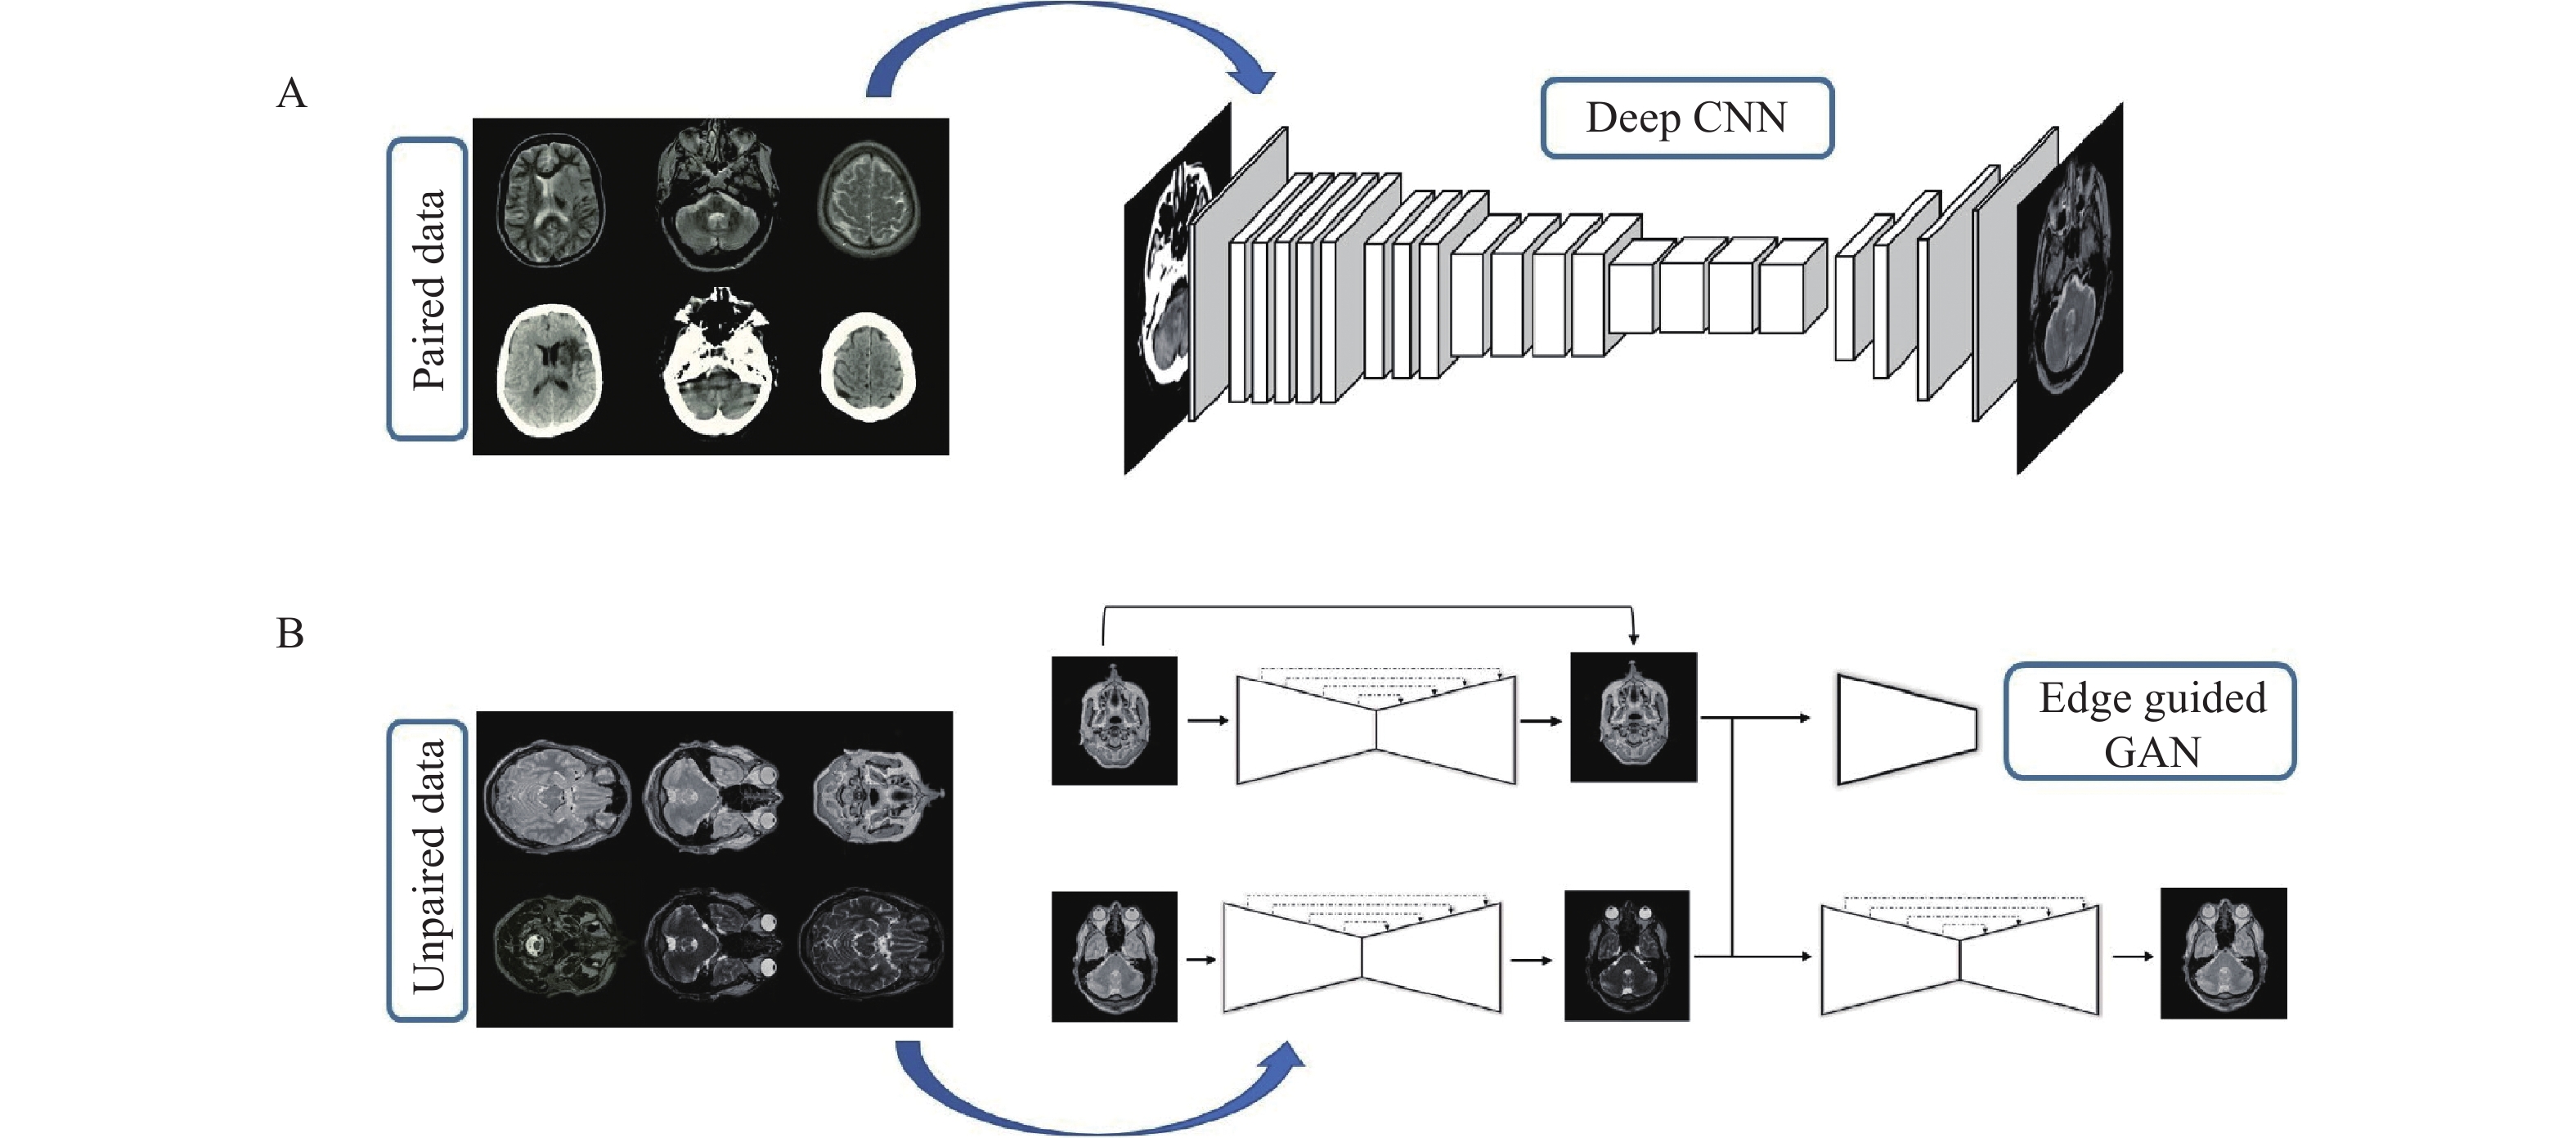

In this section, the proposed deep framework for medical image-to-image translation is presented. Fig. 1 provides a visual representation of the proposed deep framework for both paired and unpaired data by an example of the CT-MRI and T2-PD translation.

This network is proposed for image-to-image translation of unpaired data and has a structure based on the GAN. The basic structure of the proposed edge-guided GAN is represented in Fig. 4 with an example of the CT-MRI translation. As shown in Fig. 4, the proposed model has three main elements including the generator, edge detector, and discriminator. The generator learns to generate fake images by incorporating feedback from the discriminator. The proposed encoder-decoder network is utilized as the generator.

The discriminator tries to decide whether the results produced by the generator are considered the target. PatchGAN[22] is used as a discriminator in a consistent manner with the original CycleGAN, which is a multi-layer CNN for feature extraction and classification. Edges are important parts of an image, which is vital for accurate image retrieval. Hence, the edge detection network is employed to modify structural estimates by analyzing image edges of the input domain. A network-based upon U-Net[23] is trained using images and their corresponding edges, which are extracted by a canny edge detector. The trained network with fixed weights is used in the proposed EGGAN for computing the edge maintenance loss.